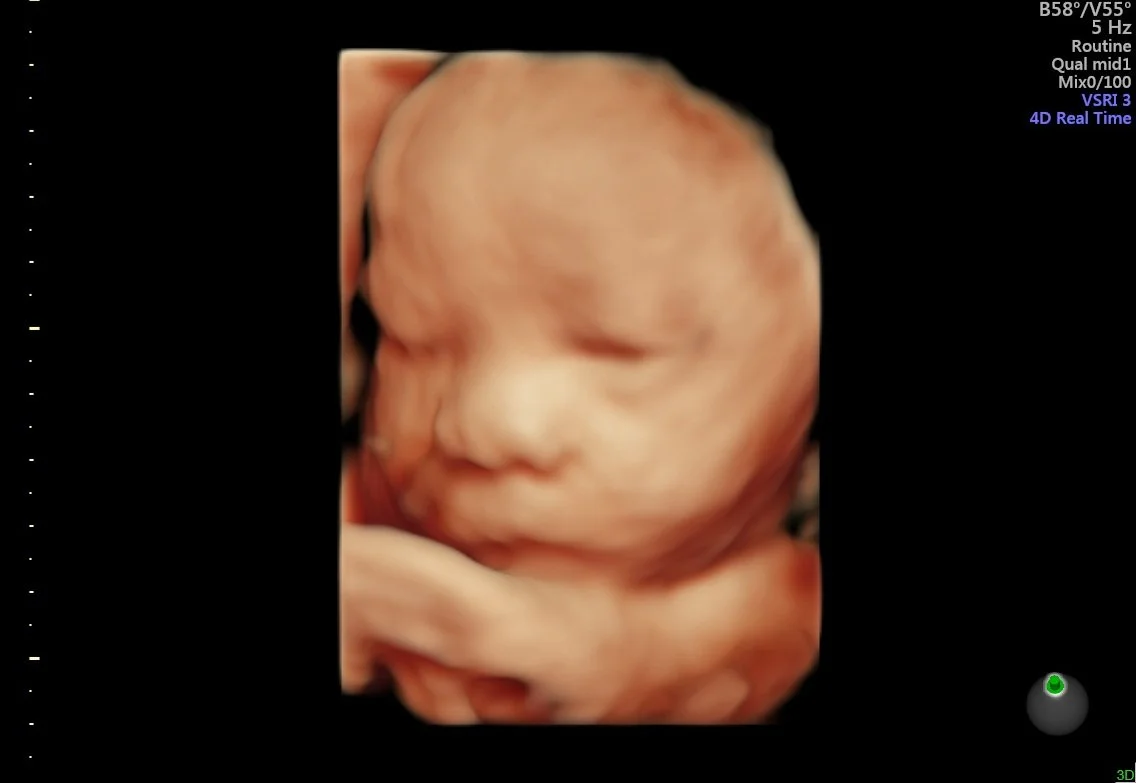

Our state of the art technology allows us to see your baby in a whole different way! With HD Live imaging, we can watch your baby wiggle, smile and yawn all in real time!